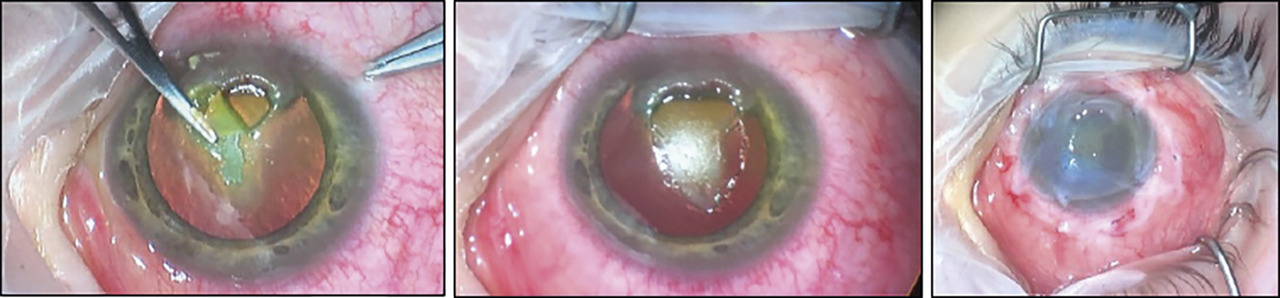

Une kératite ponctuée superficielle supérieure peut, dans les formes les plus sévères, se compliquer d’un ulcère vernal – épithélial, ovalaire, à bords nets et à fond clair – classiquement localisé en regard des papilles géantes sous-tarsales. Cette atteinte cornéenne est quasiment constante lors des poussées. Lorsque le fond de cet ulcère est comblé par un dépôt blanc, grisâtre, on parle de plaque vernale (fig. 5), qui peut évoluer vers une cicatrice responsable d’astigmatisme et d’amblyopie.

Prise en charge de la plaque vernale : grattage chirurgical à la lame ou au couteau sous anesthésie ou photokératectomie thérapeutique (fig. 6). La chirurgie des papilles géantes, par cryothérapie, voire résection avec application de mitomycine, décrite par certains auteurs, n’est plus recommandée.